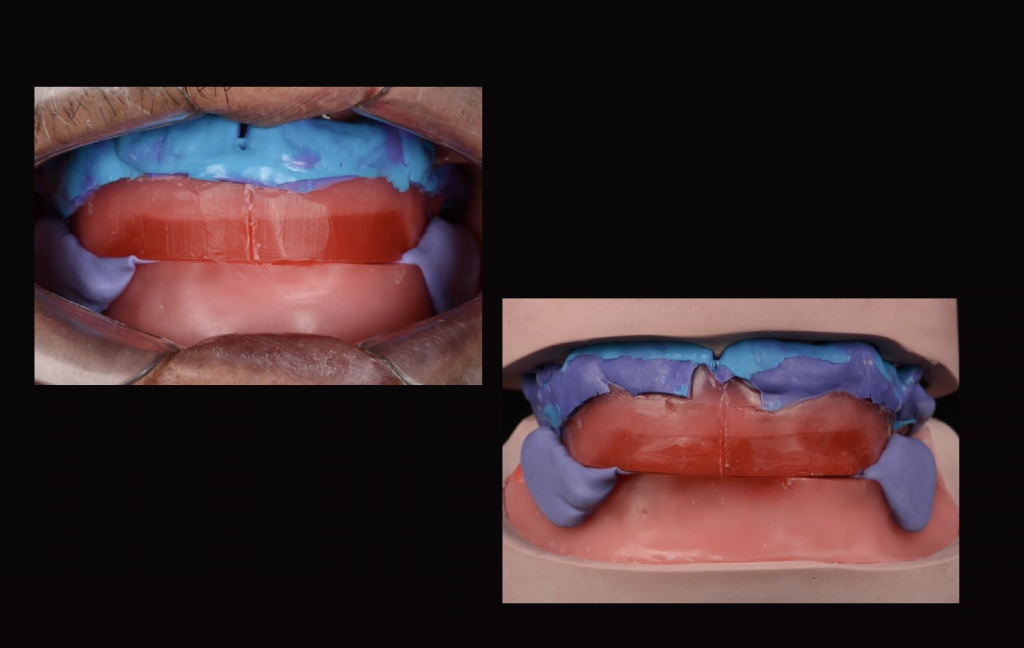

Para conseguir una succión efectiva la toma de impresión preliminar y definitiva es importante realizar la impresión a boca cerrada. De esta forma la saliva de debajo de la base de la prótesis se descarga en ese momento que está en oclusión y genera una presión negativa al sellar el borde de la prótesis a su alrededor con los tejidos móviles.

Al abrir la boca, la almohadilla retromolar se estira posteriormente cambiando la forma por una almohadilla más fina, y se contrae, se acorta y redondea al cerrar la boca. Al tomar la impresión en boca cerrada, la base de la prótesis controla la deformación de la almohadilla retromolar, sin perder el sellado posterior.

La prótesis debe adaptarse a los movimientos funcionales de la mandíbula. La presión negativa se genera al entrar los dientes en oclusión e instruirse ligeramente desde la posición de reposo. La succión de la dentadura mandibular ocurre en este momento, por lo que es crucial tomar una impresión que se ajuste en armonía con los movimientos del paciente.